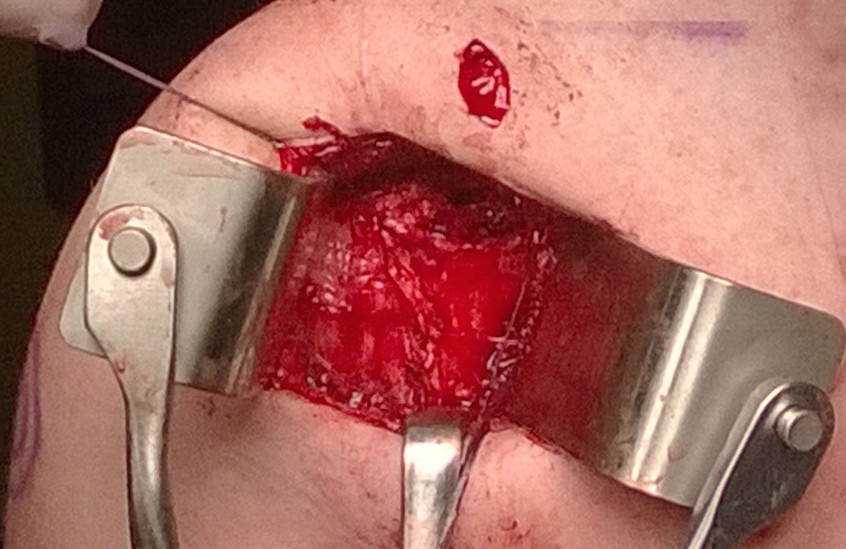

Open capsular plication

Open anterior capsular plication with subscapularis tenotomy and lateral advancement / Putti Platt

Open posterior approach in beach chair with detachment of deltoid

Infraspinatus tenotomy

Open posterior capsular plication in lateral position